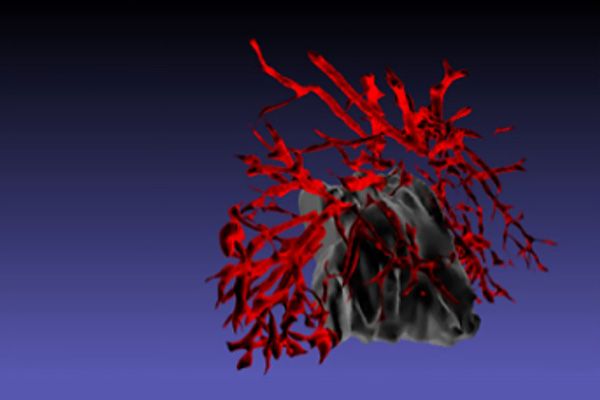

Area covered by inflammatory microglia in the brain of Alzheimer’s disease mice without (left) and with EP2 targeting drug treatment (right).